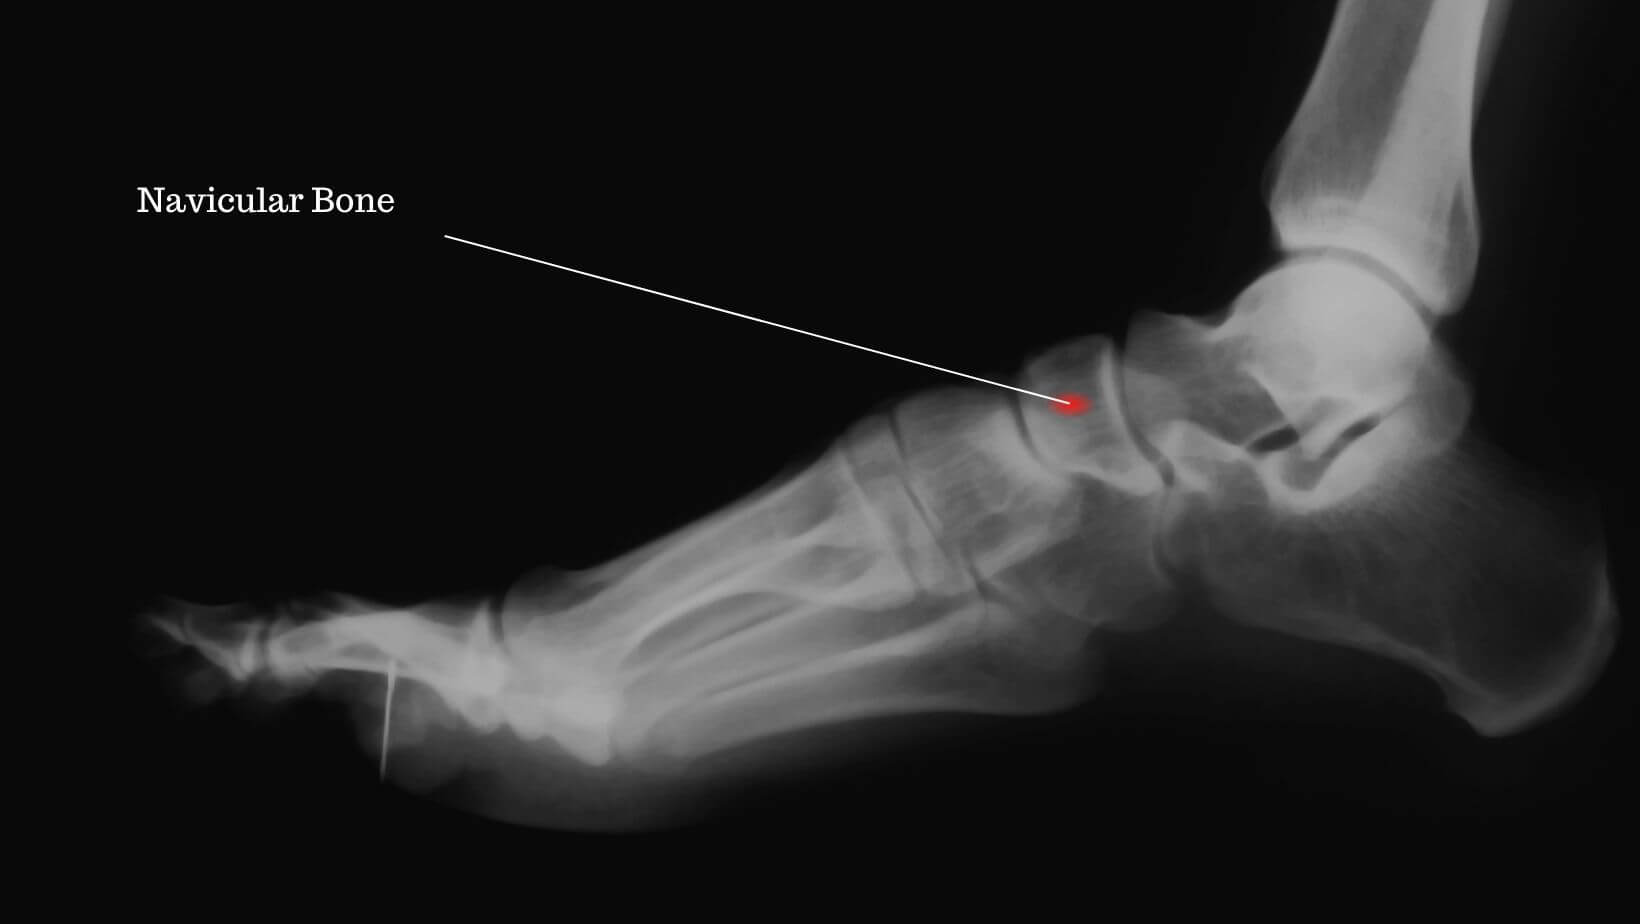

Os naviculare перевод

Os naviculare перевод 144 фотографий